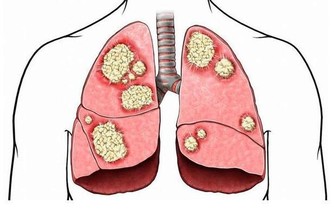

在吃飽、穿暖都成問題的時代,很少有人得糖尿病、腫瘤、癌症,為何在現代卻多了起來?

如果把這些都看成是“濁毒”,似乎就很容易理解了,實際上這些病都是吃出來的。

對於人體來說,這部分營養無法被消化,也無法被利用,但這並不意味著它們沒用。這時身體內的不法分子,如潛在的腫瘤因子等就會接收這些“廢物”,供自己享用,一旦時機成熟就會變成令人談之色變的腫瘤。